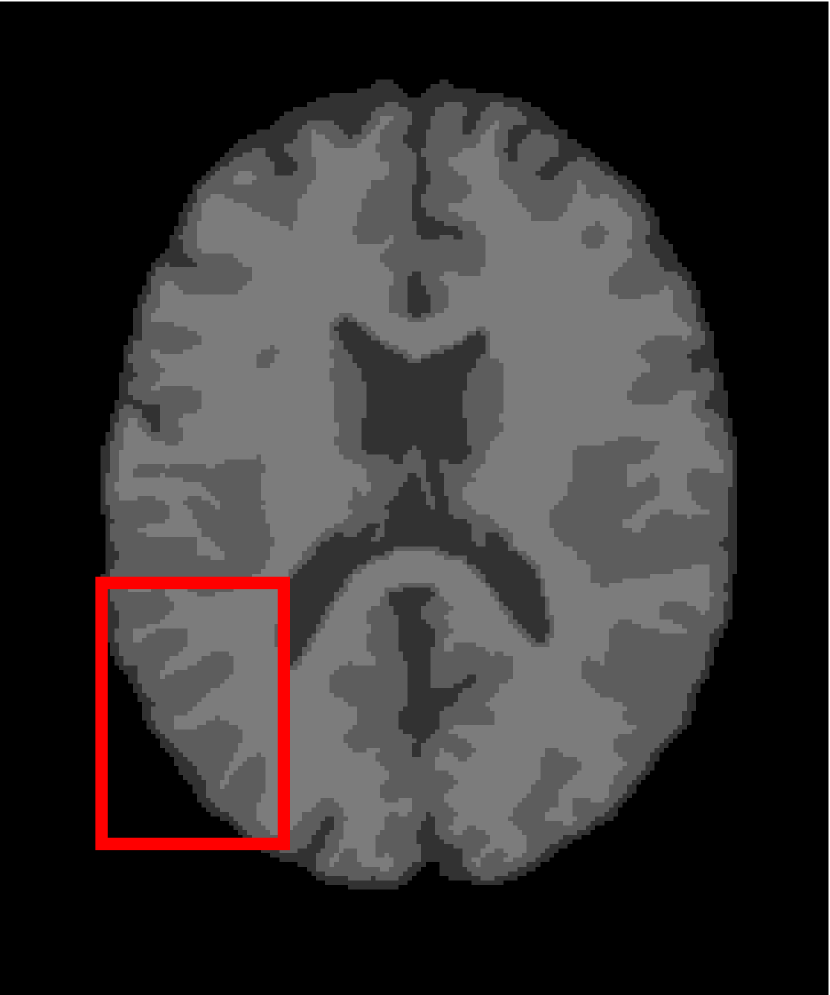

Next, we representatively segment five medical images from BrianWeb. They are represented as five slices in the axial plane with a sequence of 70, 80, 90, 100 and 110, which are generated by T1 modality with slice thickness of 1mm resolution, 9% noise and 20% intensity non-uniformity. Here, we set c=4𝑐4c=4 for all cases. The comparison between WRFCM and its peers are shown in Fig. 9 and Table II. The best values are in bold.

Figure 9: Segmentation results on five medical images. The parameter: ϕ=5.35italic-ϕ5.35\phi=5.35. From top to bottom: noisy images, ground truth, and results of FCM_S1, FCM_S2, FLICM, KWFLICM, FRFCM, WFCM, DSFCM_N, and WRFCM.

By a view of the marked red square in Fig. 9, we find that FCM_S1, FCM_S2, FLICM, KWFLICM and DSFCM_N are vulnerable to noise and intensity non-uniformity. They give rise to the change of topological shapes to some extent. Unlike them, FRFCM and WFCM achieve sufficient noise removal. However, they produce overly smooth contours. Compared with its seven peers, WRFCM can not only suppress noise adequately but also acquire accurate contours. Moreover, it yields the visual result closer to ground truth than its peers. As Table II shows, WRFCM obtains optimal SA, SDS and MCC results for all five medical images. As a conclusion, it outperforms its peers visually and quantitatively.